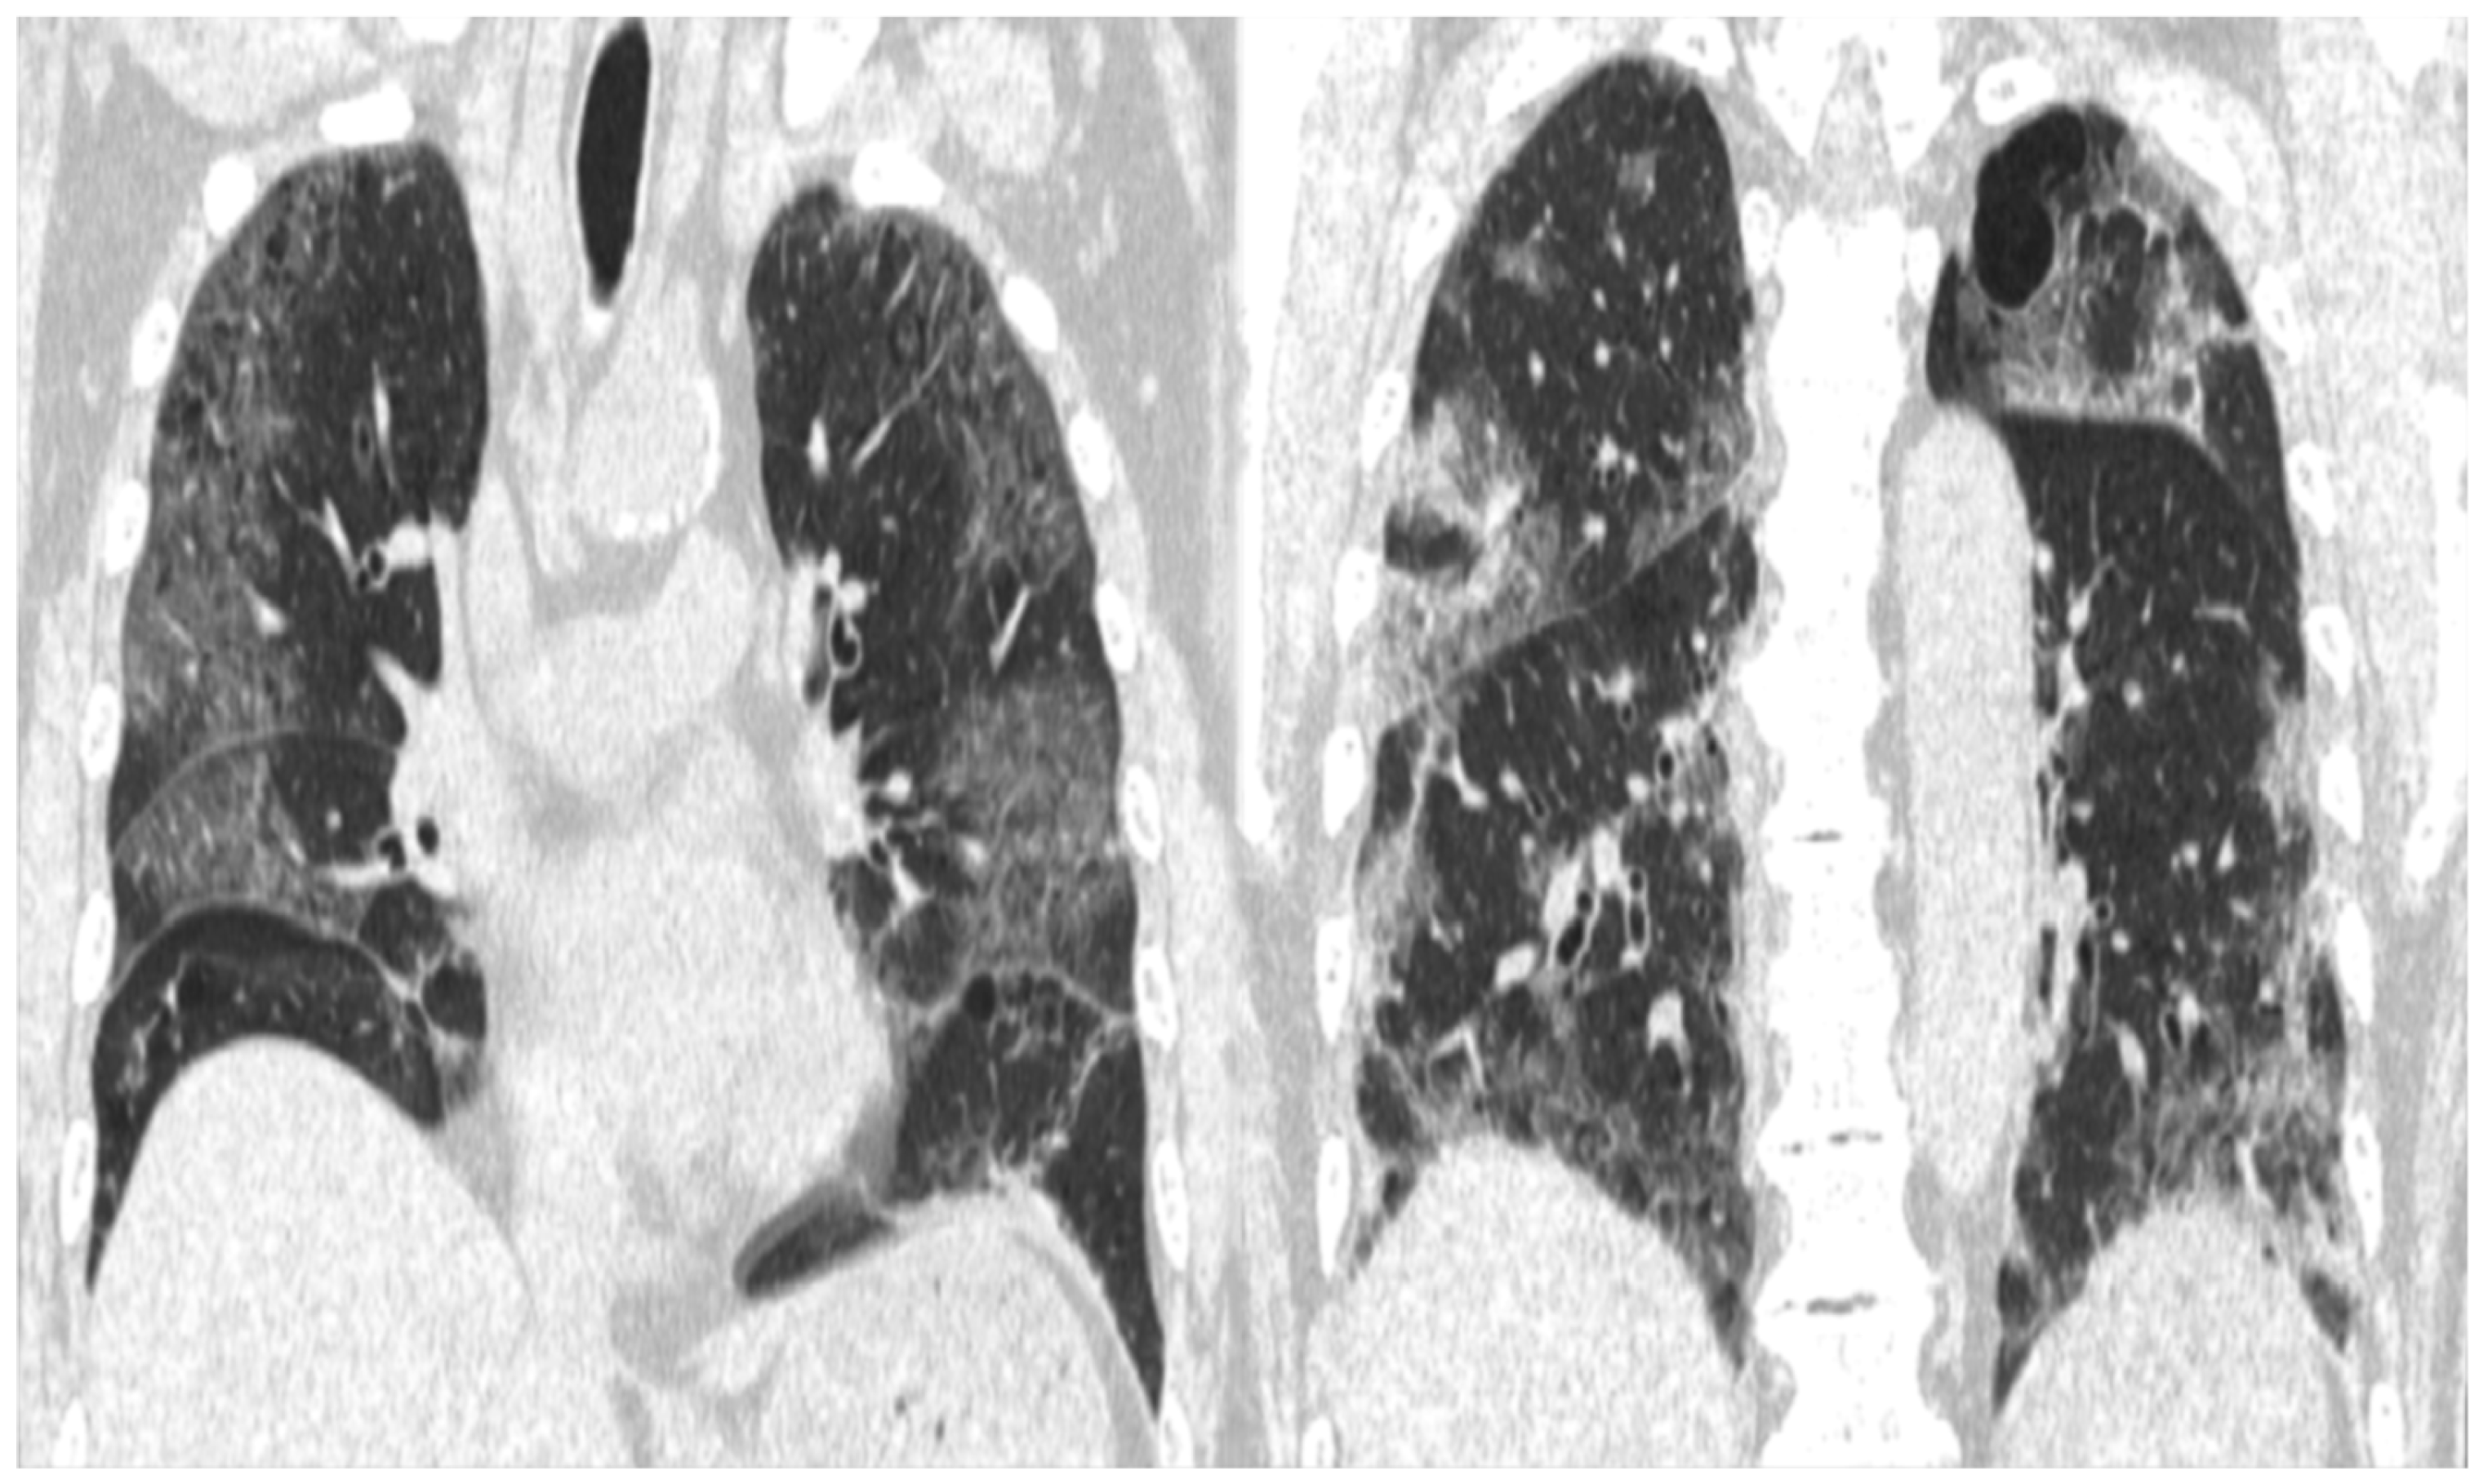

2. Case Presentation